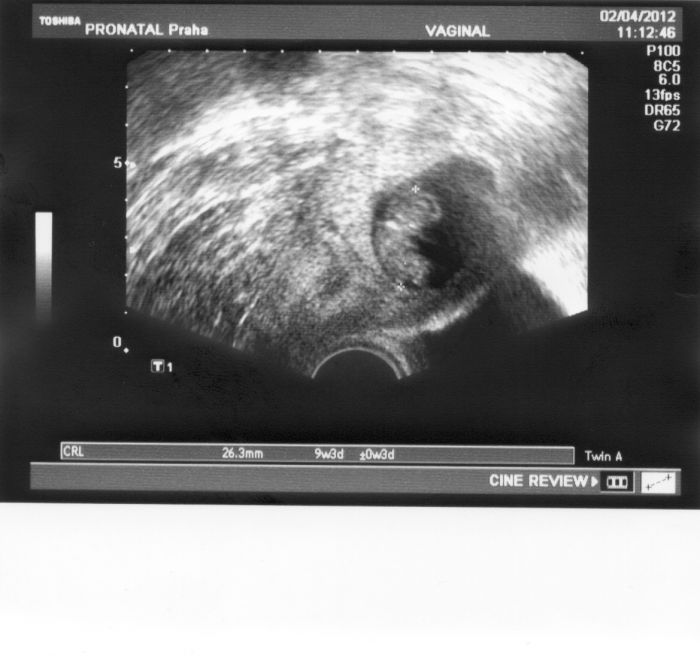

Posílám Vám všem obrázek na povzbuzení, aby jste také už brzy měli takový

Obrázek je krásnej - ten mimísek je tam už uplně vidět

[130155] jé, už to na té fotce vidím - 9+3

Leno, dneska už jsem 9+6tt. Ono je tam i napsáno plus, mínus 3dny. I minule vycházelo na UZ mimi o jeden den menší. Myslím, že dost záleží na tom, jak se tam trefí ty křížky, protože stačí o milimetřík vedle a už je to o pár dní jinak